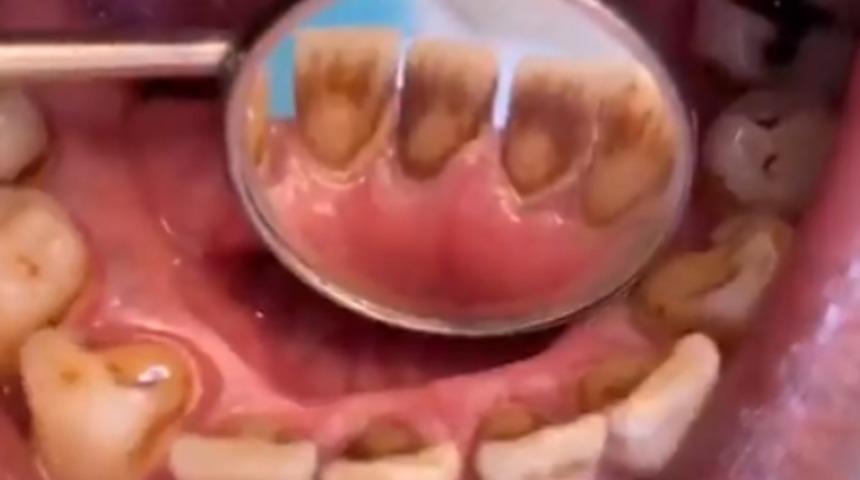

TikTok hesabından paylaştığı videoda bir hastanın ağzının içini gösteren Dr. Maryam Hadian, “'sigara içenlerin dişleri' böyle görünüyor” dedi. TikTok'ta yayınlanan videoda, her dişte koyu kahverengi lekelenme görülüyor, ön alt kısımdaki iki arka kısım neredeyse tamamen kaplanmış durumda. Doktorun paylaştığı video yarım milyondan fazla beğeni aldı.

Tütündeki nikotin ve katranın dişleri çok kısa sürede sarardığı ve çok sigara içenlerin yıllarca sigara içtikten sonra dişlerinin kahverengi veya griye döndüğünü görebileceği iyi bilinmektedir.